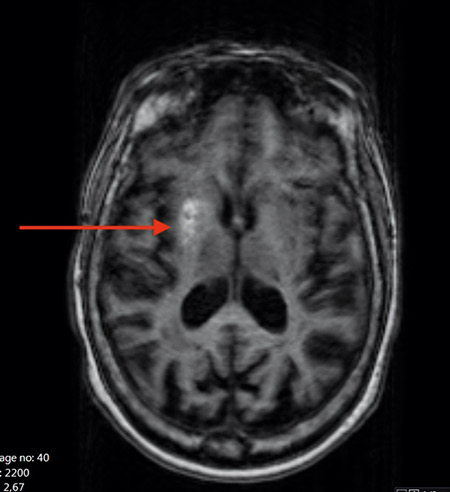

Vidare utredning gjordes med EEG och MRT av hjärnan (Figur 3). EEG dag 2 visade ingen epileptiform aktivitet men en lätt förlångsammad postcentral grundrytm samt episodisk förlångsammad aktivitet över vänster hemisfär. MRT visade en hög signal i höger putamen på T1-viktade bilder men ingen kontrastuppladdning eller diffusionsinskränkning i det beskrivna området.

Figur 3. MRT av hjärnan i T1-sekvens hos patienten i fallbeskrivningen knappt 2 månader efter den ursprungliga hyperglykemiepisoden visar, trots måttligt med rörelseartefakter, ökad signal i de tidigare beskrivna områdena i basala ganglier på höger sida.